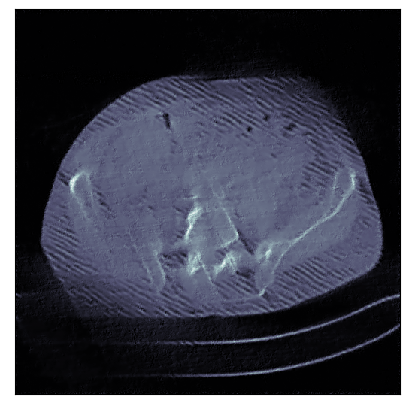

We consider the variational reconstruction framework for inverse problems and propose to learn a data-adaptive input-convex neural network (ICNN) as the regularization functional. The ICNN-based convex regularizer is trained adversarially to discern ground-truth images from unregularized reconstructions. Convexity of the regularizer is desirable since (i) one can establish analytical convergence guarantees for the corresponding variational reconstruction problem and (ii) devise efficient and provable algorithms for reconstruction. In particular, we show that the optimal solution to the variational problem converges to the ground-truth if the penalty parameter decays sub-linearly with respect to the norm of the noise. Further, we prove the existence of a sub-gradient-based algorithm that leads to a monotonically decreasing error in the parameter space with iterations. To demonstrate the performance of our approach for solving inverse problems, we consider the tasks of deblurring natural images and reconstructing images in computed tomography (CT), and show that the proposed convex regularizer is at least competitive with and sometimes superior to state-of-the-art data-driven techniques for inverse problems.